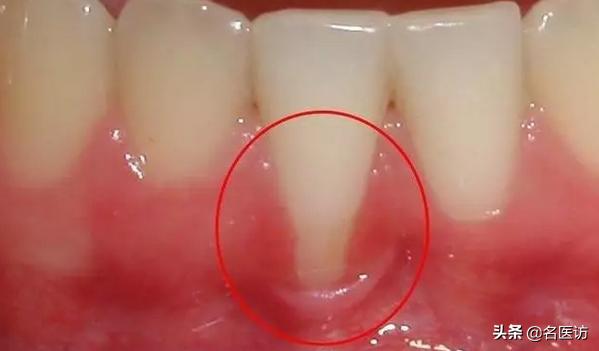

牙周炎

牙周炎会导致牙槽骨吸收,从而使牙龈萎缩,牙根外露。

牙根的表面是没有牙釉质覆盖的,一旦牙根没有了牙龈的保护,就容易在刷牙时受到磨损,同时会对冷、热、酸的刺激敏感。